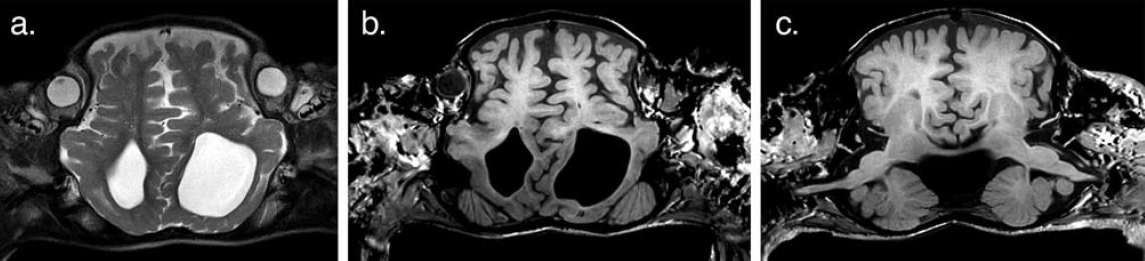

Sziámi ikrek születése irodalmi ritkaság. Ötvenezer szülésre jut egy sziámi ikerpár. Még kevésbé gyakoriak a fejüknél összenőtt sziámi ikrek. A koponyáknál összenőtt konstelláció, a craniopagus – mely gyakran együtt jár az agyak összenövésével - mindössze 2-5% az összes összenőtt ikrek között, azaz 2,5 millió szülésre számítva fordul elő 1 ilyen eset. Sikeres szétválasztásuk pedig igazi, világirodalmi ritkaság. Ezért egy-egy eset közlése nem csak érdekes esemény, de rendkívül fontos is, hiszen a megoldás módszerei az egész orvostudomány számára tanulságosak lehetnek. A bangladesi craniopagus ikrek a Stone és Goodrich osztályozás szerinti az I. típusú totalis verticalis összenövésben voltak (1. ábra).

1. ábra.

A craniopagus ikrek: Rabeya és Rukaya

2/a,b,c. ábra.

2018-ban készült MRI képek az ikrek összenőtt, interdigitáló agyállományáról és koponyájáról.

Pataki Gergely és Csókay András megvizsgálták a gyermekeket, részletesen áttanulmányozták az eset addigi dokumentációját. Első véleményük nekik is kedvezőtlen volt. A craniopagus ikreknek bár külön-külön agya volt egy interthalamicus összekötő tractussal, és a két agy tekervényei szinte hézagmentesen, a szorosan összekulcsolt kézujjakhoz hasonlóan kapcsolódtak össze (2/ a,b,c. ábra). Emiatt, egy esetleges műtéti kísérletnél a szétválasztási kísérlet, komolyabb sérülés nélkül, szinte lehetetlennek látszott. Másrészt, bár az agyakat ellátó érrendszer artériái elkülönültek, a vénáknál viszont hatalmas, közös, sagittalis vénás sinus volt. Irodalmi adatokból ismerték, hogy ebből a műtét során, hatalmas, sőt végzetes kimenetelű vérzés keletkezhet, mint ahogy erre már volt is példa craniopagus ikreknél, s emiatt az ikerpár mindkét tagja meghalt (Szingapúri eset – Riffles Hosp; 2003).